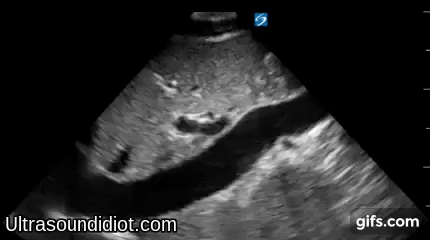

Parasternal Exam 2